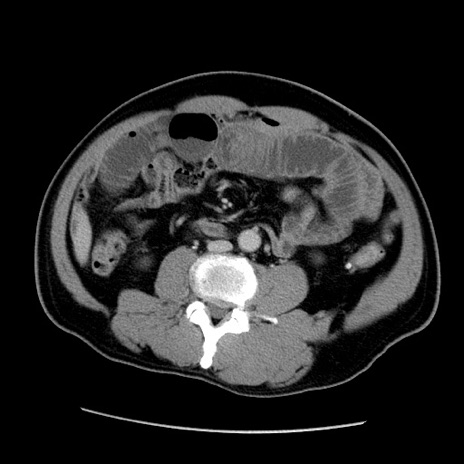

冠状断像

症例22(横断像)

【症例】50歳代男性

【主訴】腹痛

【現病歴】AVMからの被殻出血のため回復期リハ病棟入院中。 本日午後3時頃急に下腹部痛が出現した。

【既往歴】AVM、被殻出血、虫垂炎、高血圧

【身体所見】意識晴明、左半身不全麻痺、会話の理解は良好、36.5°C、腹部:膨隆、全体に板状硬、下腹部正中に圧痛点あり、反跳痛-、筋性防御不明、右下腹部にope scar

【データ】WBC 9400、CRP 0.06